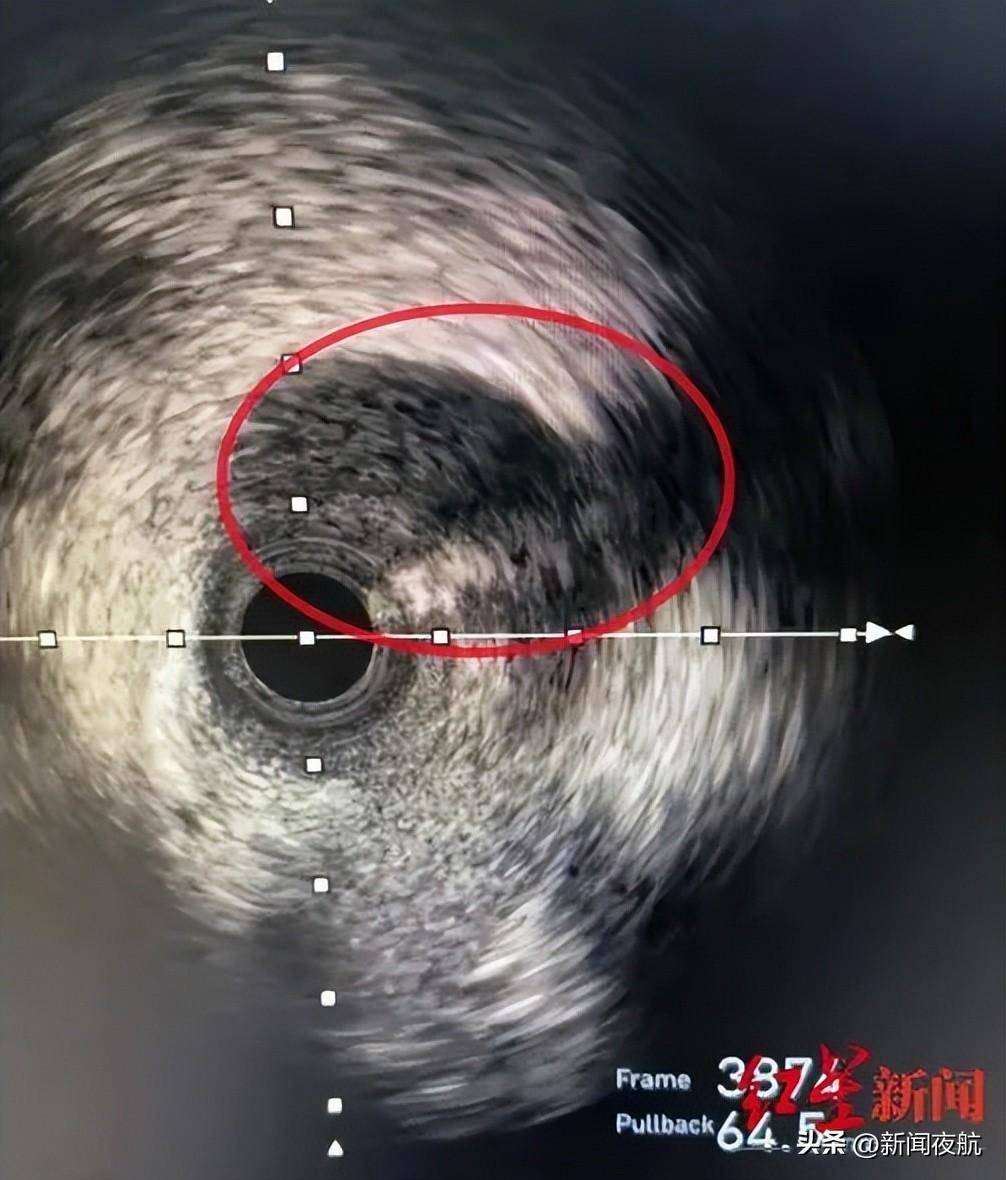

血管表现出“断层式的狭窄”,这不是常规的动脉粥样硬化疾病表现。在迅速判断后,心血管内科胸痛急诊团队又为王女士开展了腔内影像学IVUS(冠状动脉血管内超声)进一步检查并精准找到了病因——前降支血管夹层影像,俗称自发性冠脉动脉夹层(SCAD)。简单来说,就是血管内壁有撕裂,漏出的血液被尚还完好的血管外壁兜着,犹如自行车胎“鼓包”。